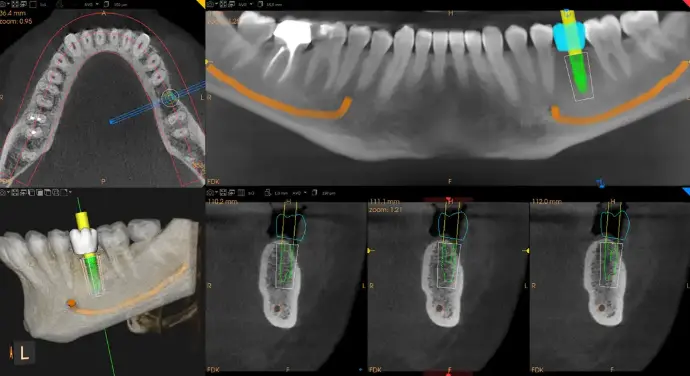

Precision Powered by Technology

At AVF Dental Group, we utilize the latest diagnostic tools to ensure your procedure is safe, predictable, and comfortable. Our in-house lab ensures that every crown is a work of art, custom-milled to the highest specifications.

Digital Planning

The dentist checks your teeth and gums to ensure whitening is safe and effective.